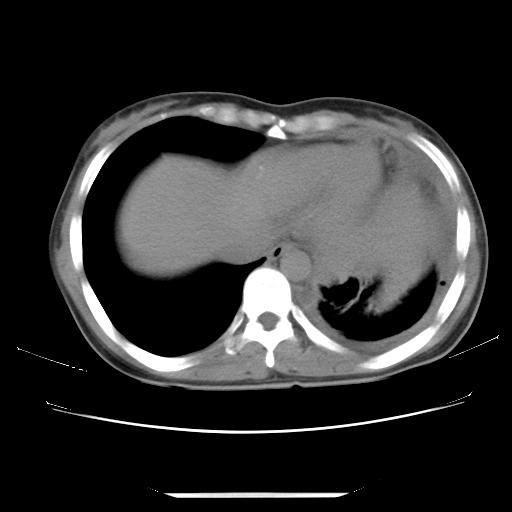

左肺上叶不张,左侧胸水,叶间裂积液,纵隔淋巴结,脾脏钙化,考虑左肺上叶支气管内膜结核,结核性胸膜炎,脾结核

支持两肺继发性肺结核,左侧胸膜腔包裹性积液、胸膜肥厚,脾内多发钙化(结核钙化)。

支持 两肺继发性肺结核,左侧胸膜腔包裹性积液、胸膜肥厚;脾内多发钙化(结核钙化)。

两肺继发性肺结核,左侧胸膜腔包裹性积液、胸膜肥厚;脾内多发钙化(结核钙化)。支持!

左肺上叶不张,左侧胸水,叶间裂积液,纵隔淋巴结,脾脏钙化,考虑左肺上叶支气管内膜结核,结核性胸膜炎,脾结核。支持!